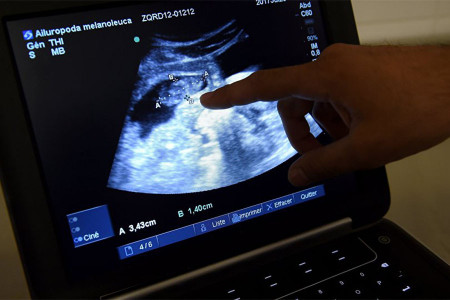

Salgın sırasında, korona hastaları dışında farklı sebeplerle hastanelere başvurması gereken kişiler de erişimde sorunlar yaşıyor. Bunların arasında kürtaj yaptırmak isteyen kadınlar da var.